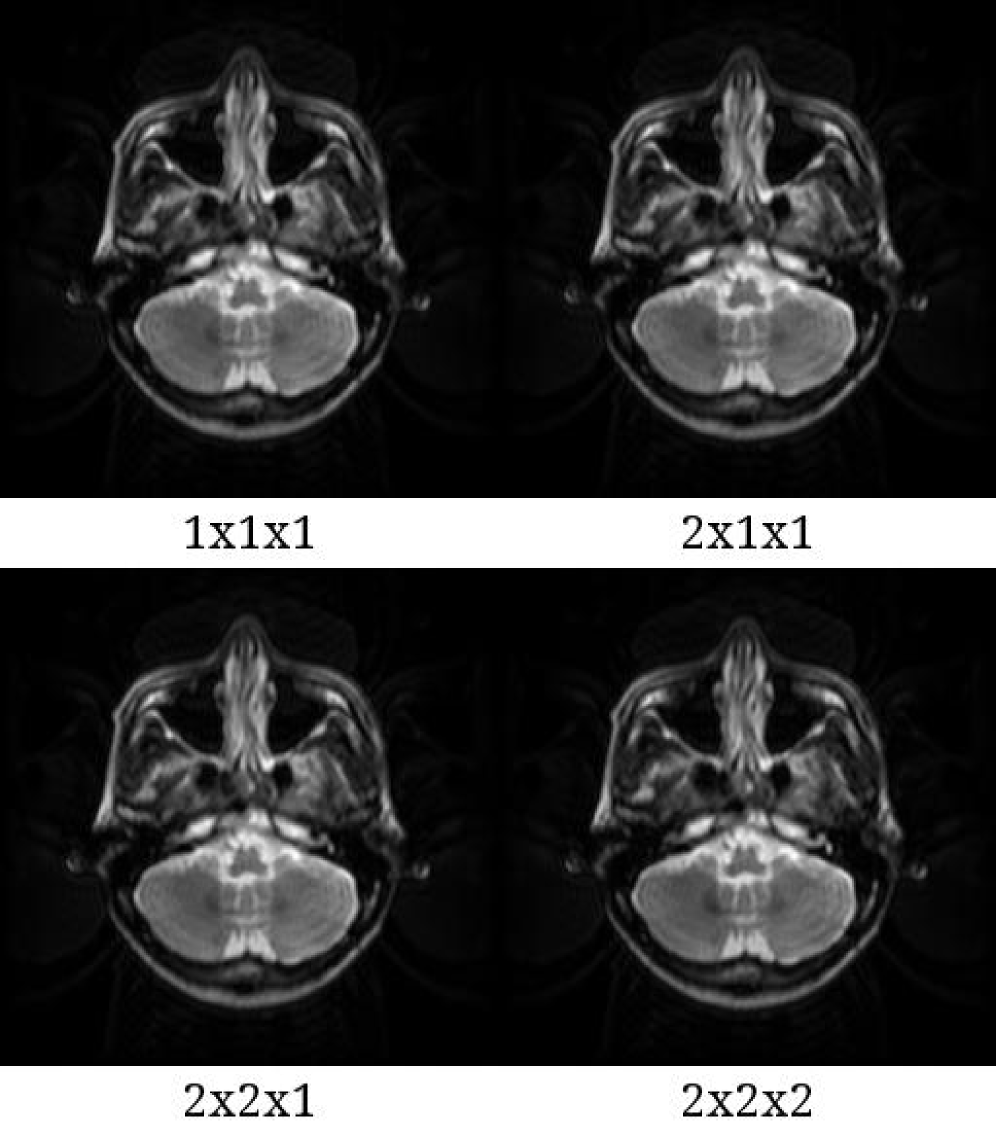

[Uncaptioned image]

Figure S5. Reconstructed images with 4 subvoxel types in the case of an EPI sequence. The three numbers of the types represent the numbers of divided subvoxels in x, y, and z directions. The images were reconstructed with a gridding algorithm. Abbreviations: EPI, echo-planar imaging.